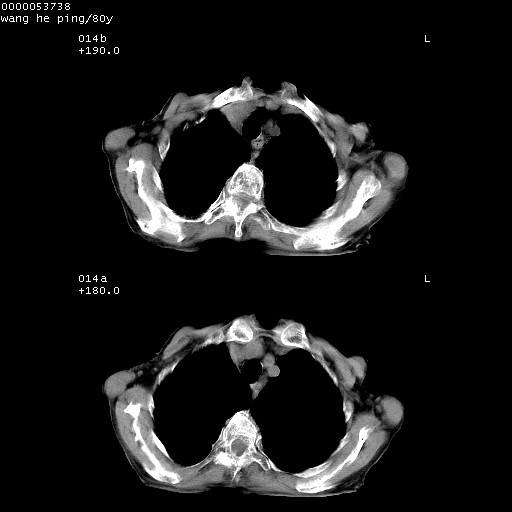

以下是引用黑白光影在2008-8-28 22:33:00的发言:[br]右肺中央型肺癌伴阻塞性肺炎,肺癌肺转移。

以下是引用lshx在2008-8-28 22:06:00的发言:[br]1.右肺中心型肺癌伴阻塞性肺炎,不除外双 肺早期转移。[br]2.心包积液。

以下是引用随光逐影在2008-8-29 7:40:00的发言:[br]1)右肺中心型肺癌伴阻塞性肺炎,肺内转移。2)心包积液(少量)。

以下是引用wqs571018在2008-8-28 21:56:00的发言:[br]右肺中心型肺癌伴阻塞性肺炎可能。

以下是引用liuyue在2008-8-28 22:46:00的发言:[br]1.右肺中心型肺癌伴阻塞性肺炎。[br]2.心包积液(少量)。